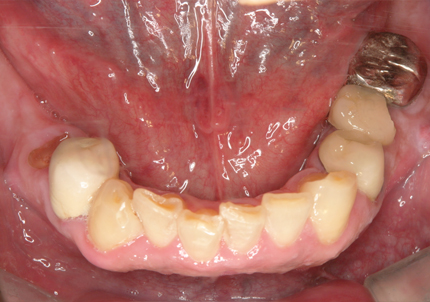

1.初診時口腔内写真(2014年6月)